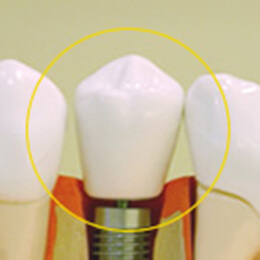

上部構造

上部構造(人工歯冠)

一般的「歯」と呼ばれる天然歯の歯冠に相当する部分で上部構造とよばれているものです。

白い素材が主となり、材質は、力の強く加わる奥歯以外は、審美性・機能性の観点からセラミックが多く用いられます。

上部構造(クラウン)の装着

歯茎が回復したら、口の中と歯の型を取り、歯並びや形状、歯の色などを調べて、インプラントに連結させるセラミック製の人工歯を作ります。

約2~3週間後、最終的な歯が完成したら、いよいよ装着。ここで治療は一旦完了となります。